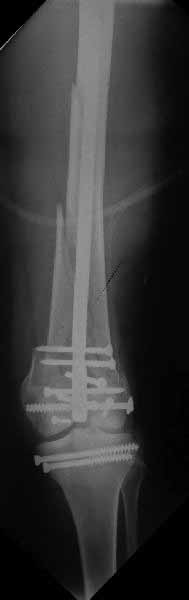

Ответ на эту часть Вашего поста – вложенный файл. Больная оперирована неделю назад по поводу открытого перелома дистального эпиметафиза бедренной кости. После операции она идёт в рентгенкабинет для выполнения послеоперационной контрольной рентгенографии, представленной на слайдах 10 и 11. Узнав, почему её фотографируют, просила передать Вам, Антон, привет.

Позволю себе напомнить коллегам ещё раз, что являюсь сторонником антеградного остеосинтеза при переломах дистального эпиметафиза бедренной кости. Такая приверженность основана не на преимуществах внесуставного введения стержня или большем проценте положительных результатов. Она основана на возможности обеспечить блокирование на минимальном расстоянии от суставной поверхности в нескомпрометированной кости и, таким образом стабилизировать максимально низкие переломы. В приведенном Вами случае самый дистальный из блокирующих винтов проведен на расстоянии более 2 см от конца стержня. Из-за того, что к стержню присоединяется кондуктор, на стержне теряется 1-1,5 см его длины, где можно было разместить отверстия для блокирования. И что более важно, вместе с потерянной для этой цели длиной стержня утрачивается для размещения блокировочных винтов, пожалуй, самая ценная часть дистального эпиметафиза бедренной кости. Проблемы дистального блокирования в разных плоскостях, локализации точки ввода стержня при антеградном остеосинтезе – это всё решаемые технические проблемы. Но антеградный остеосинтез низких дистальных переломов бедра при адекватном блокировании в нескомпрометированной кости обеспечивает решение стратегической задачи – стабильный остеосинтез и возможность нагрузки.